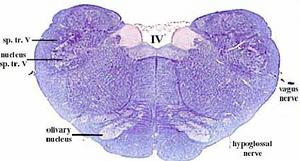

secciones transversales a diferentes niveles del tronco del encéfalo mostrando la localización de los núcleos neuronales eferentes de los nervios craneales

EFERENTES:

somatoeferentes (SE) : inervan músculos esqueléticos

visceroeferentes(VE): parasimpáticos